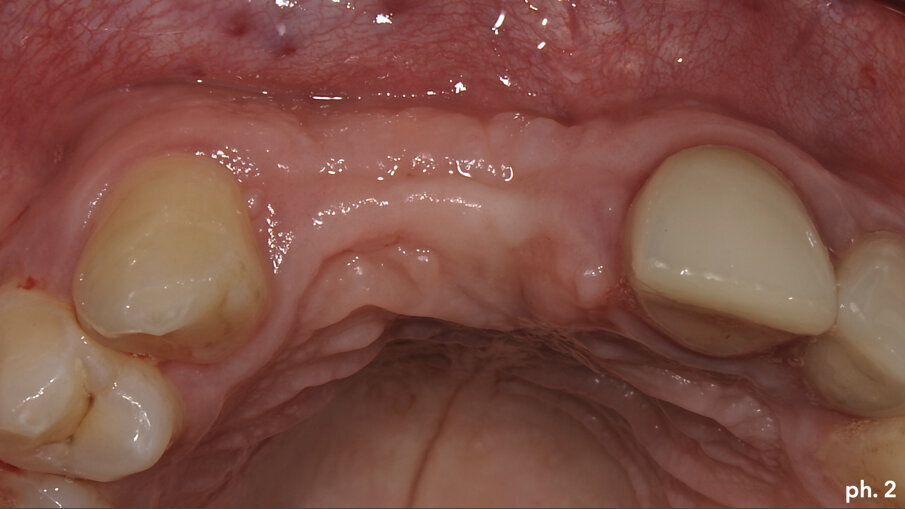

Il paziente, maschio caucasico di 28 anni, si presenta alla nostra osservazione in seguito a un incidente che ha provocato l’avulsione traumatica degli elementi 1.1 e 1.2 con conseguente riduzione dei volumi ossei della zona che, oramai, risulta parzialmente edentula. Sono inoltre presenti in corrispondenza degli elementi 2.1 e 2.2, anch’essi coinvolti nel trauma, due elementi provvisori in resina. La richiesta del paziente è quella di riabilitare la zona edentula con impianti e finalizzazione protesica da 1.2 a 2.2 con corone singole in ceramica1, 2. Dall’esame clinico si evidenzia una carenza di tessuto osseo sia in senso verticale (Fig. 1) che in senso orizzontale (Fig. 2). Si è deciso quindi che l’opzione terapeutica migliore per ottenere una buona rigenerazione ossea di tipo combinato, fosse quella di utilizzare una griglia in titanio customizzata3 in combinazione con un mix di osso bovino deproteinizzato (Geistlich Bio-Oss) e chips ossei prelevati nella zona operata tramite l’utilizzo di un un safe-scraper (Meta)4, il tutto ricoperto da uno strato di matrice Mucograft. Il protocollo operativo delle griglie in titanio customizzate Yxoss CBR prevederebbe l’utilizzo di una membrana in collagene come Geistlich Bio-Gide nella ricopertura della stessa. Personalmente in alcuni casi da me trattati ho deciso di sostituire la membrana in collagene con la matrice, sempre in collagene di origine suina ma in questo caso ricostituito, soprattutto nei settori estetici laddove è richiesta una maggiore quantità di tessuto cheratinizzato al fine di ottenere un risultato estetico migliore. Una volta esposto quindi il tessuto osseo (Figg. 3, 4), si è provveduto ad effettuare una serie di perforazioni a livello della corticale ossea al fine di favorire un regolare sanguinamento (Fig. 5): questo permetterà ai nostri materiali da rigenerazione di usufruire di una maggiore quantità di fattori di crescita, proteine morfogenetiche, ed ottenere quindi una loro migliore integrazione nel tempo.